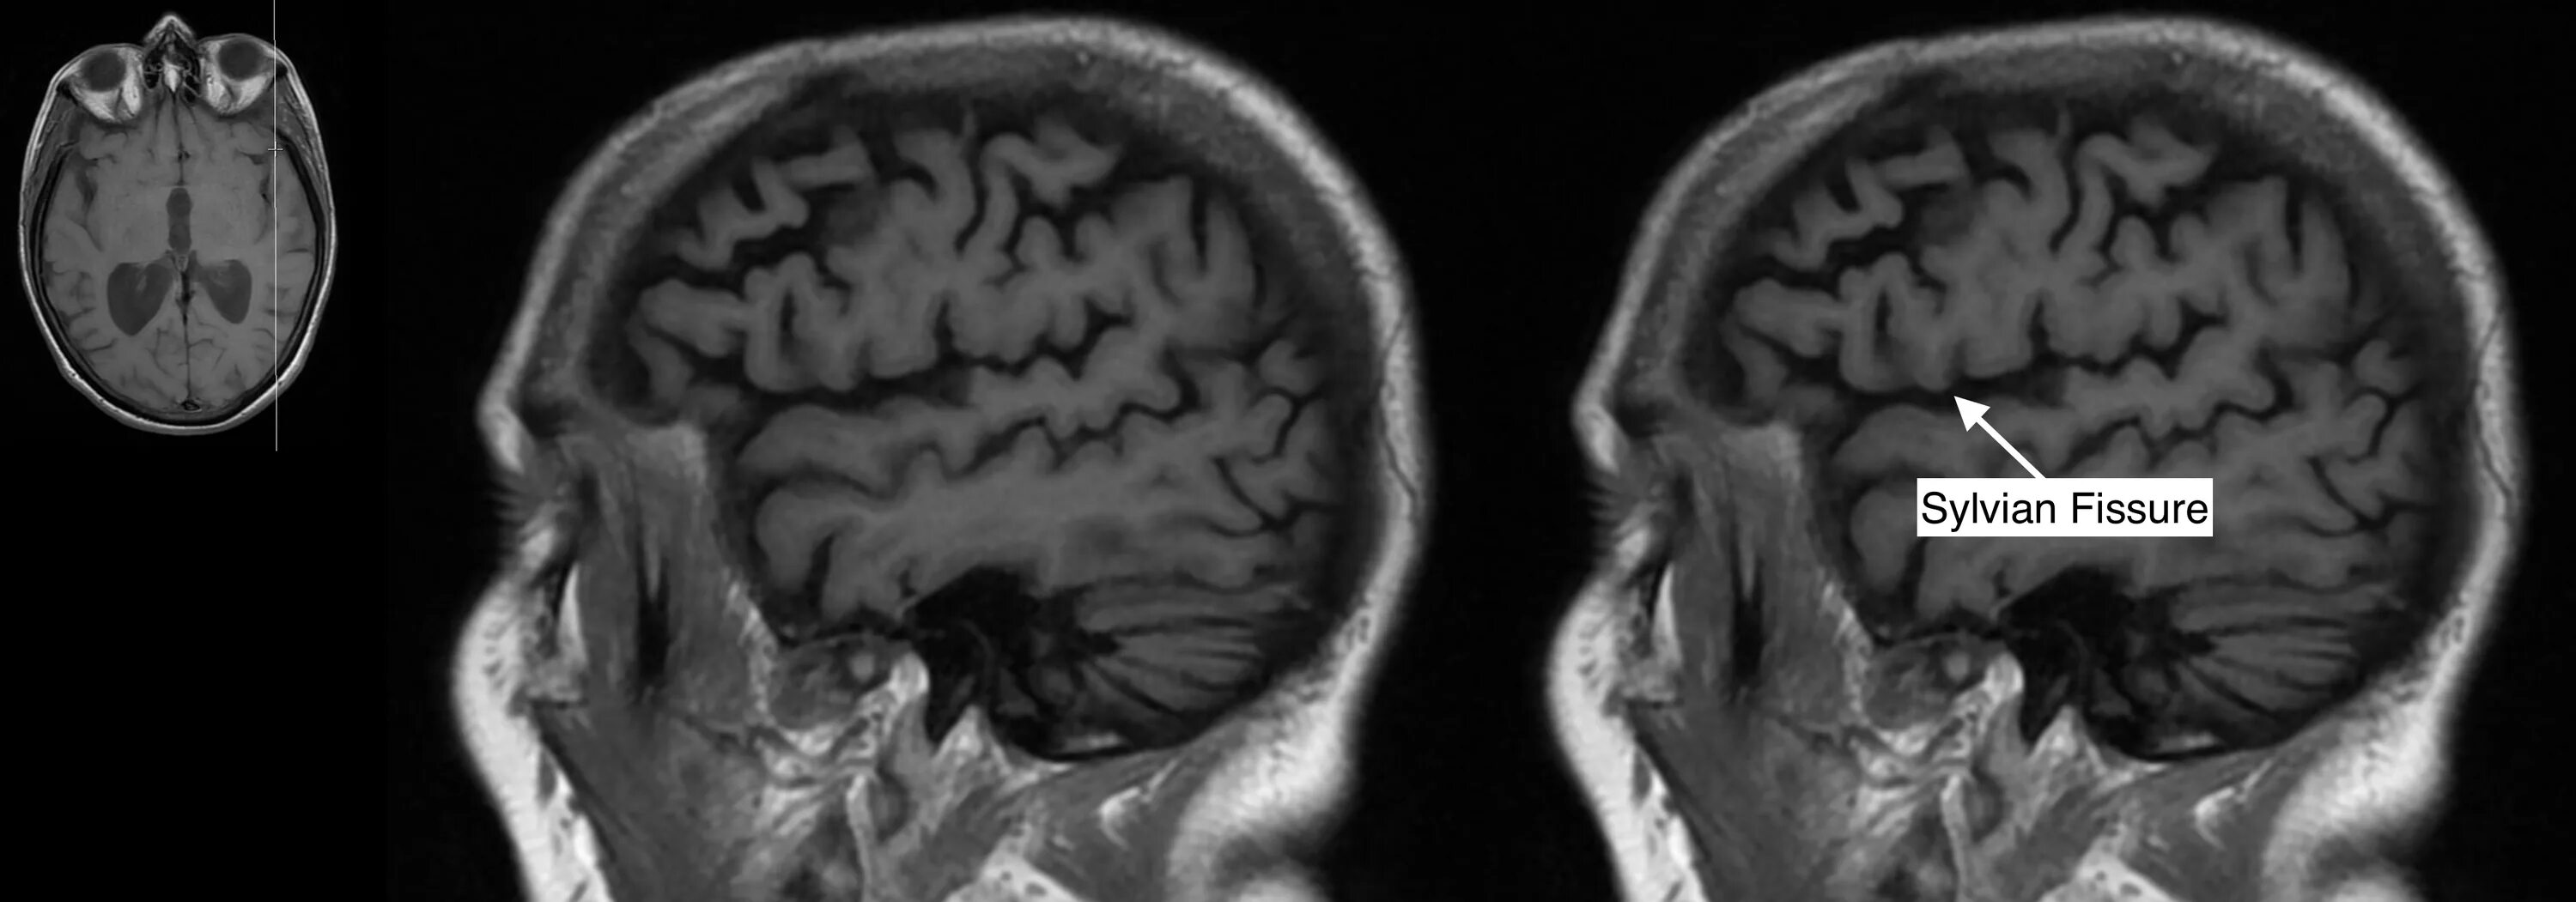

Pars orbitalis